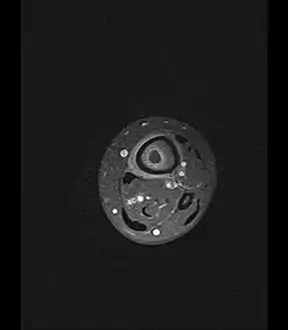

Oval, elliptical, or serpentine radiolucency usually greater than 1 cm surrounded by a heavily reactive sclerosis, granulation tissue, and a nidus often less than 1 cm. The margins often appear scalloped on radiograph. Brodie's abscess is best visualized using computed tomography (CT) scan. Associated atrophy of soft tissue near the site of infection and shortening of the affected bone. Osteoblastoma may be a classic sign for Brodie's abscess.